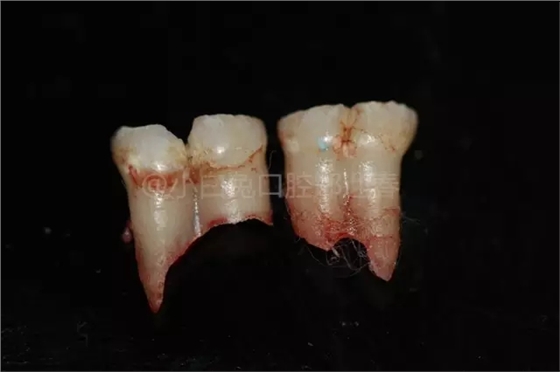

患兒,10歲,因上前牙未替換來診,查體:輕度反合,51和52、61和62均融合,且存在間隙約4mm,全面曲面斷層片顯示:11、21未萌,52、51、61、62牙根均有不同程度的生理性吸收。

拔出后的離體牙